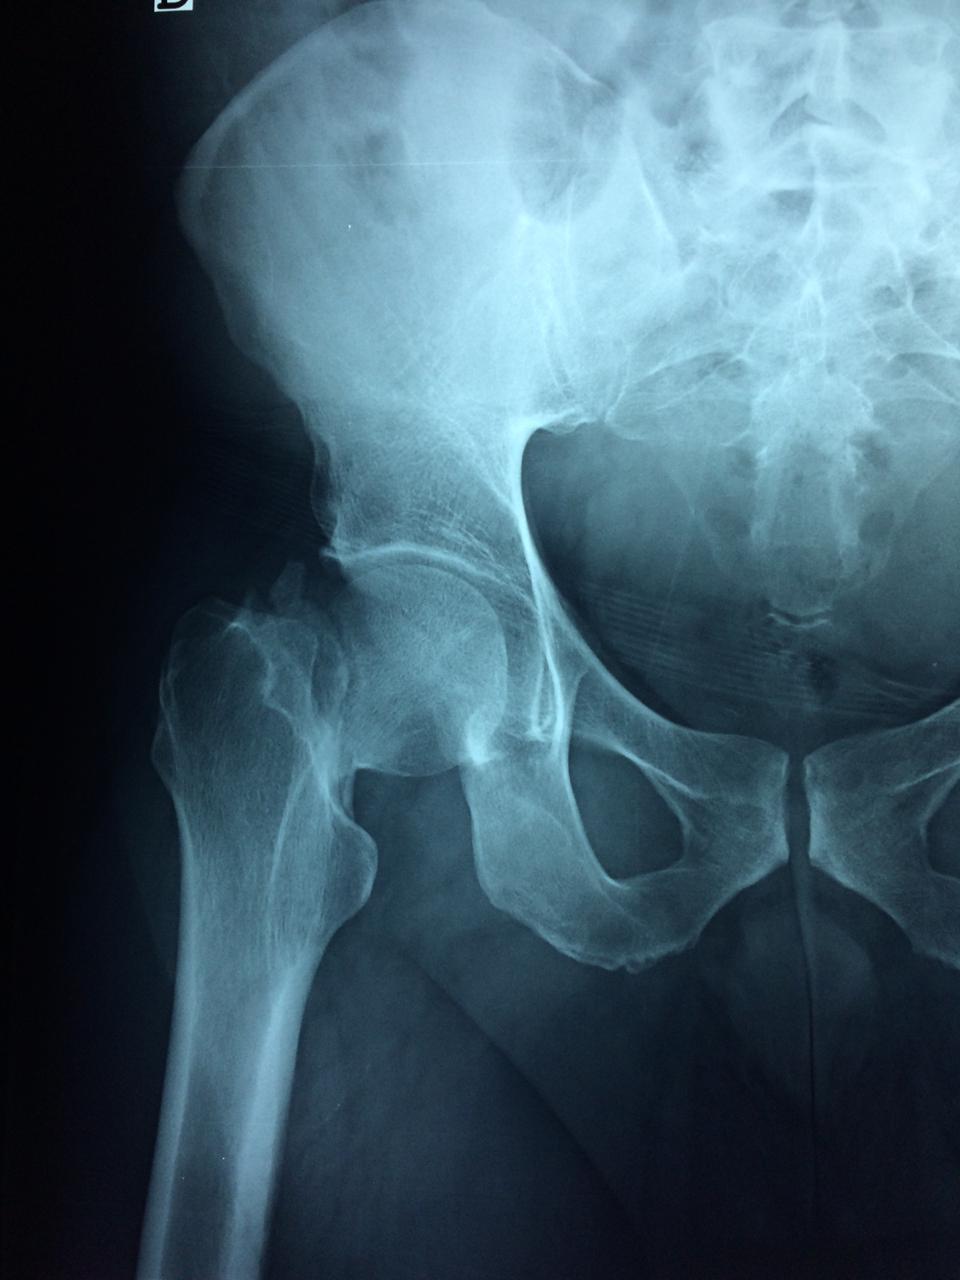

La cirugía de fractura de cadera se realiza para reparar una ruptura en la parte superior del hueso del muslo. Este hueso se denomina fémur.

Es parte de la articulación coxofemoral. Si una fractura de cadera no recibe tratamiento, es posible que deba permanecer en una silla o en la cama.

Esto puede llevar a otros problemas de salud potencialmente mortales, sobre todo si usted es una persona mayor.